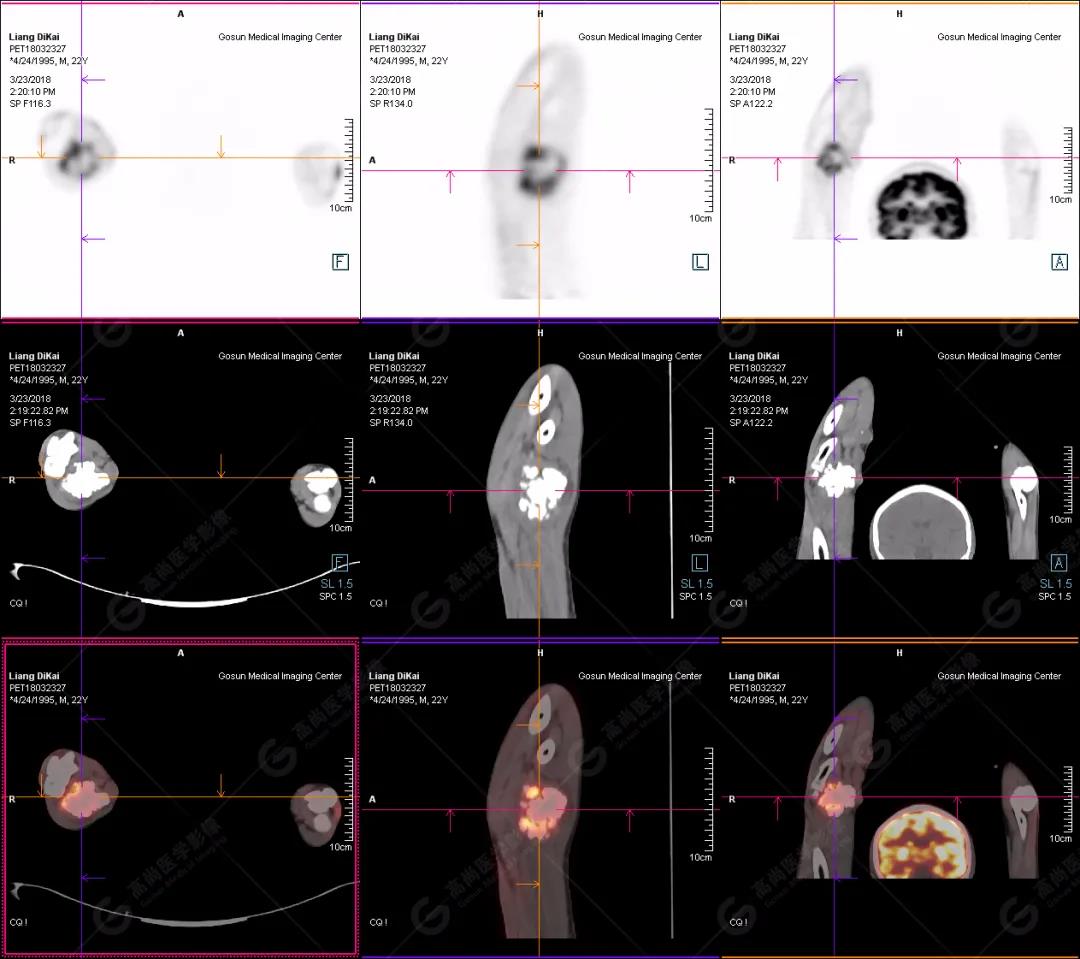

本中心PET/CT提示

1.右肘關(guān)節(jié)周圍、骶尾部皮下、雙側(cè)臀部、盆腔左側(cè)壁及左側(cè)大腿根部肌肉、肌間隙多發(fā)結(jié)節(jié)狀、片塊狀及不規(guī)則巨塊狀高密度鈣化灶,伴代謝不均勻輕度增高,考慮為鈣質(zhì)沉著癥;

2.甲狀腺雙葉后方多發(fā)(右2個,左1個)小結(jié)節(jié)狀軟組織影,部分代謝輕度增高,多考慮為甲狀旁腺腺瘤。